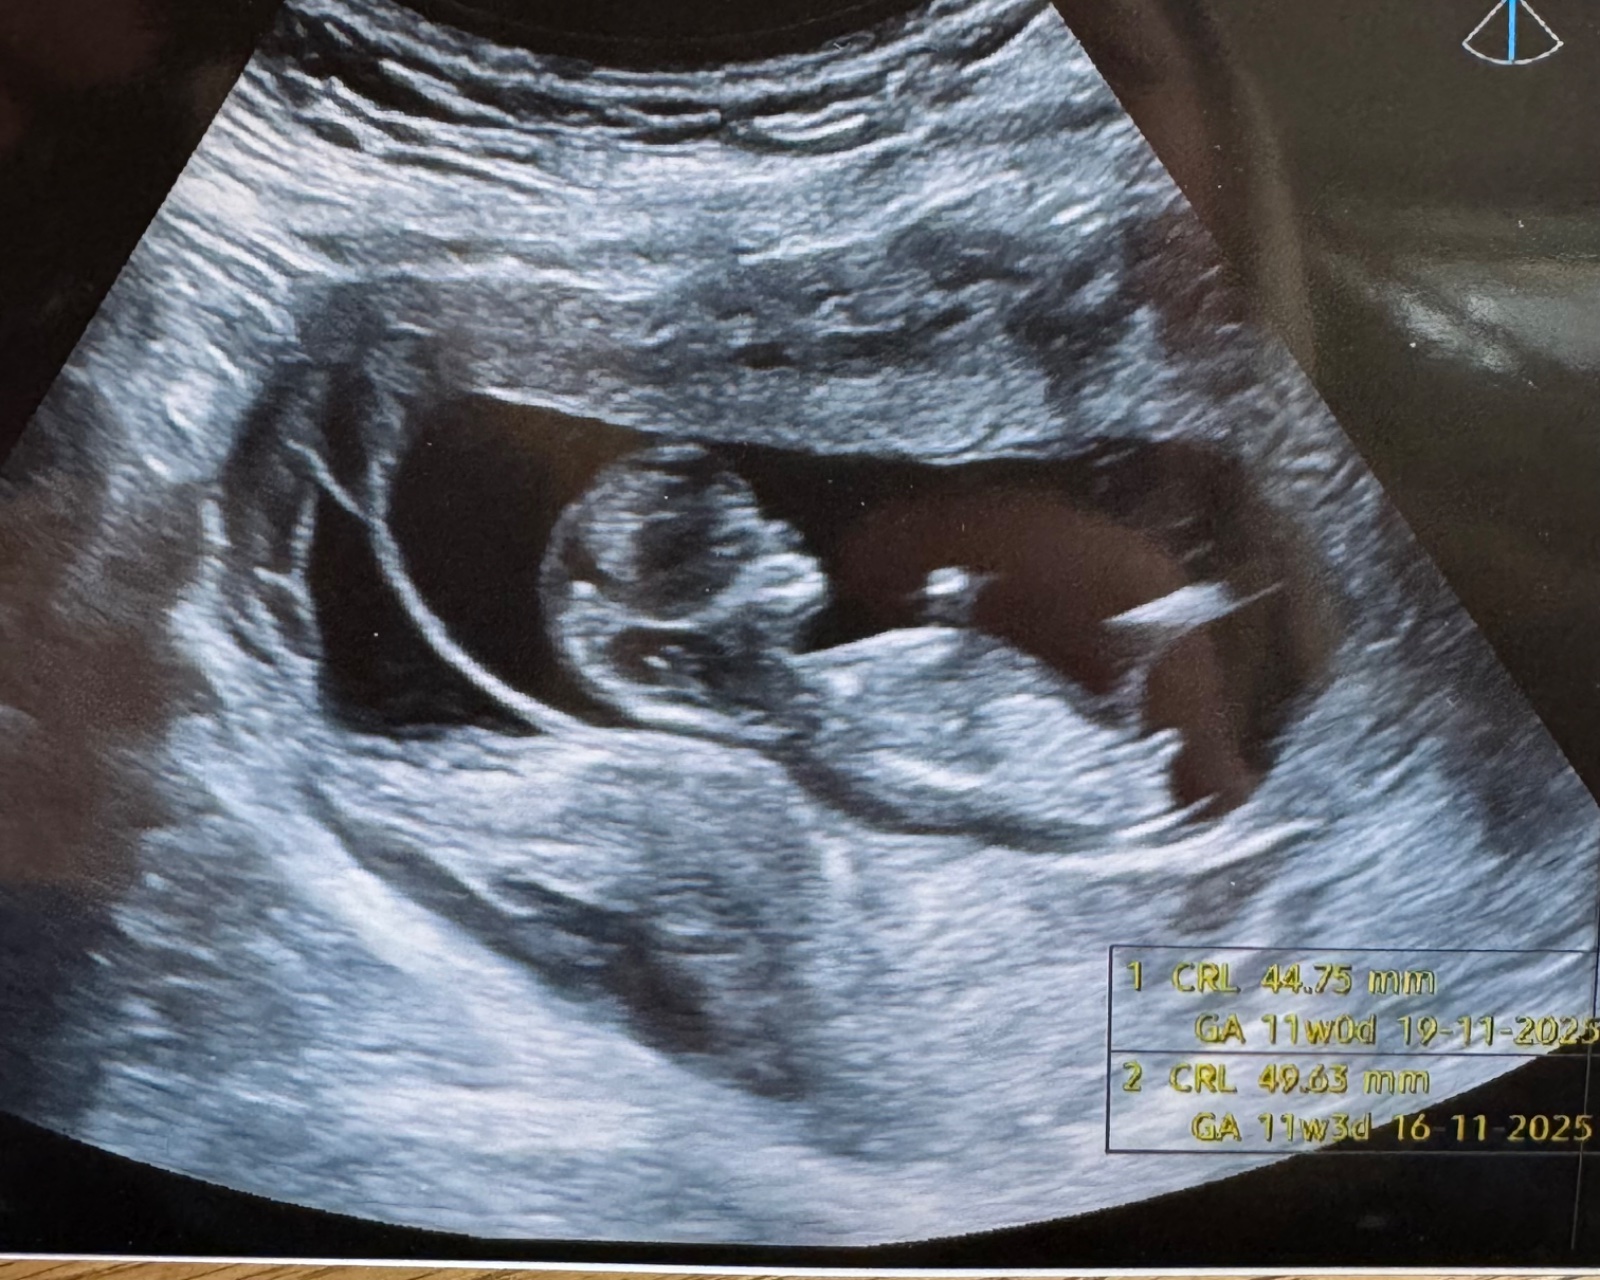

Pohlaví miminka z ultrazvuku. Lze rozpoznat?

Je to jeste dost brzy, ale podle nub teorie bych rekla holcicka.